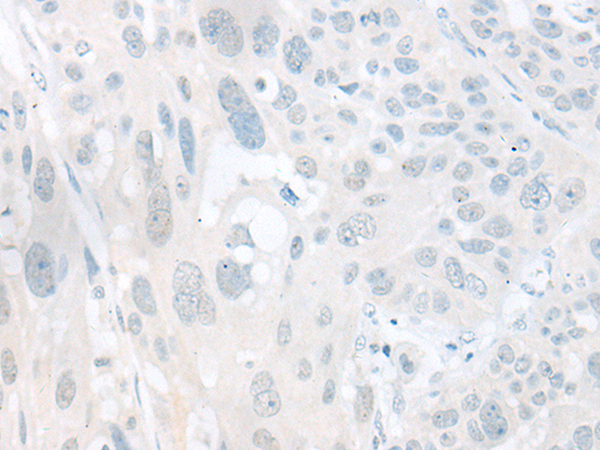

分类: 科研抗体货号: P06321别名: GY2; FKSG1; WDR14; WDVCF; DGCRK3应用: IHC反应种属: Human, Mouse